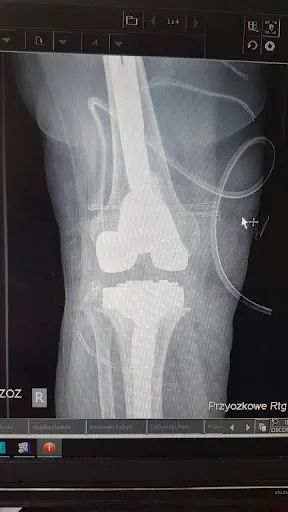

### Clinica Bogdański – ortopedia na najwyższym poziomie w Gdyni W sercu Gdyni, przy ulicy Witolda 17, działa Clinica Bogdański – specjalistyczna placówka skupiona na ortopedii. Pod wodzą dr. Michała Bogdańskiego klinika oferuje kompleksową diagnostykę i leczenie schorzeń układu ruchu, w tym skomplikowane operacje stawów biodrowych czy rekonstrukcje ścięgien, takich jak Achilles. Pacjenci chwalą sobie nie tylko fachową wiedzę, ale też przyjazną atmosferę bez zbędnego stresu. Klinika cieszy się doskonałą reputacją – średnia ocena na Google to 5.0/5 na podstawie 23 opinii, co wyróżnia ją wśród lokalnych placówek medycznych. Dr Michał Bogdański zdobył uznanie za precyzyjne diagnozy oparte na dokładnej analizie badań, jak MRI, oraz za indywidualne podejście do pacjenta. Opinie klientów podkreślają udane operacje bioder u osób starszych czy z dodatkowymi komplikacjami, np. hemofilią, a także szybką rekonwalescencję – po zabiegach pacjenci szybko wracają do codziennych aktywności, jak prowadzenie samochodu czy spacery. Personel zapewnia rewelacyjną opiekę szpitalną, a wizyty kończą się jasnymi wytycznymi rehabilitacyjnymi. Klinika oferuje też usługi z zakresu medycyny estetycznej, np. iniekcje kwasu hialuronowego, doceniane za skuteczność i przystępne ceny. Pacjenci z Gdyni i okolic, w tym Gdańska, polecają Clinica Bogdański za empatię, rzeczowość i komunikatywność doktora. To miejsce, gdzie nawet trudne przypadki kończą się pozytywnie, co potwierdzają liczne podziękowania za profesjonalizm i ludzkie podejście. (Słowa: 248)